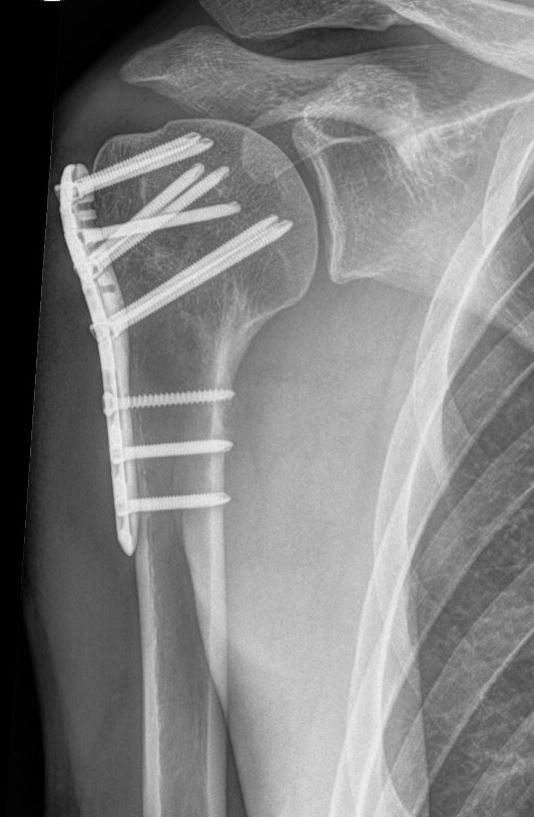

Indien u geopereerd moet worden, zal de traumachirurg de vorm van de kop willen herstellen en de kop of de fragmenten van de kop weer vast willen zetten aan de schacht. Hiervoor heeft uw traumachirurg verschillende opties, afhankelijk van het type breuk en de voorkeur van uw chirurg. Vaak gebruikt worden platen en schroeven om de verschillende breukdelen aan elkaar vast te zetten. Soms kan de chirurg ook besluiten de breuk met een pen en schroeven vast te zetten. Hiervoor is vaak een kleinere snede nodig dan bij een plaat met schroeven.

Wanneer de kop in meerdere stukken is gebroken en uw chirurg inschat dat vastzetten met een plaat en schroeven of pen niet haalbaar is, kan het zijn dat u direct in aanmerking komt voor een kunstkop/schouderprothese. Uit onderzoek blijkt echter dat dit alleen zinvol is bij de zeer ernstige breuken en dat de functionele resultaten hiervan niet altijd even goed zijn. Welke operatie u krijgt, is dus afhankelijk van de eigenschappen van de breuk, uw eigen toestand en de voorkeur van de chirurg.

Zoals elke operatie, heeft ook een operatie voor een gebroken bovenarmsbot kans op complicaties, zoals ontstekingen van de wond, zenuwletsel en het uitbreken van het fixatie materiaal en het niet goed willen vastgroeien van de breuk. Ook hebben patiënten na een operatie nogal eens last van blijvende stijfheid van de schouder ten gevolge van verstijving van het gewrichtskapsel en inwendige littekenweefsel.